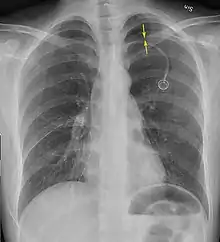

Chest X-ray showing a pneumothorax on the right (left in the image), where the absence of lung markings indicates that there is free air inside the chest

A large right-sided spontaneous pneumothorax (left in the image). An arrow indicates the edge of the collapsed lung